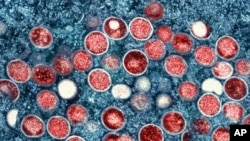

ورلڈ ہیلتھ آرگنائزیشن نے مونکی پوکس کا نام تبدیل کرکے ایم پاکس( mpox) رکھ دیا ہے۔عالمی تنظیم نےایسےخدشات کا حوالہ دیا ہے کہ دہائیوں پرانی جانوروں کی بیماری کے اصل نام کو امتیاز اور نسل پرستی سے تعبیر کیا جا سکتا ہے۔

اقوام متحدہ کے صحت کےادارے نے پیر کو ایک بیان میں کہا کہ ایم پوکس، مونکی پوکس کے لیے اس کا نیا ترجیحی نام ہے، جس میں کہا گیا ہے کہ مونکی پوکس اور ایم پوکس دونوں ہی نام اگلے سال استعمال کیے جائیں گے جب کہ پرانے نام کو مرحلہ وار ختم کیا جائے گا۔

ڈبلیو ایچ او نے مونکی پاکس کے پھیلاؤ کو عالمی ایمرجنسی قراردینے کے تقر یبأ فوراّ بعد، اس بیماری کا نام تبدیل کرنے کے بارے میں ماہرین سے مشورہ کرنا شروع کردیا تھا۔

Mpox کو سب سے پہلے monkeypox کا نام 1958 میں اس وقت دیا گیا،تھا جب ڈنمارک میں طبی تحقیق میں استعمال ہونے والے بندروں میں "پاکس جیسی" بیماری کا مشاہدہ کیا گیا۔